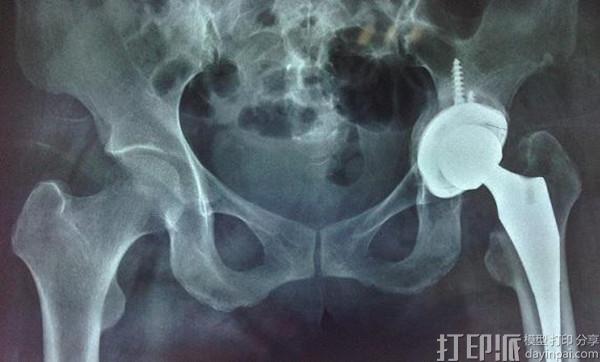

完善术前准备后, 孙鲁伟主任带领其团队,在手术室全麻下历时约70分钟成功实施了山东省首例3D打印骨小梁髋臼+CL型生物柄的人工全髋关节置换手术。术中髋臼内侧壁骨溶解缺损较重,严重处仅有薄薄一层软组织连接,股骨头旋转中心内移,髋臼内侧壁骨缺损处给予自体骨颗粒植骨,安放3D打印骨小梁髋臼+CL型生物柄时均有良好的初始稳定性。术后患者疼痛消失,髋关节屈伸活动及左下肢长度恢复满意。术后X线片复查显示,全髋关节假体位置良好,患者于术后2周切口拆线顺利康复出院。